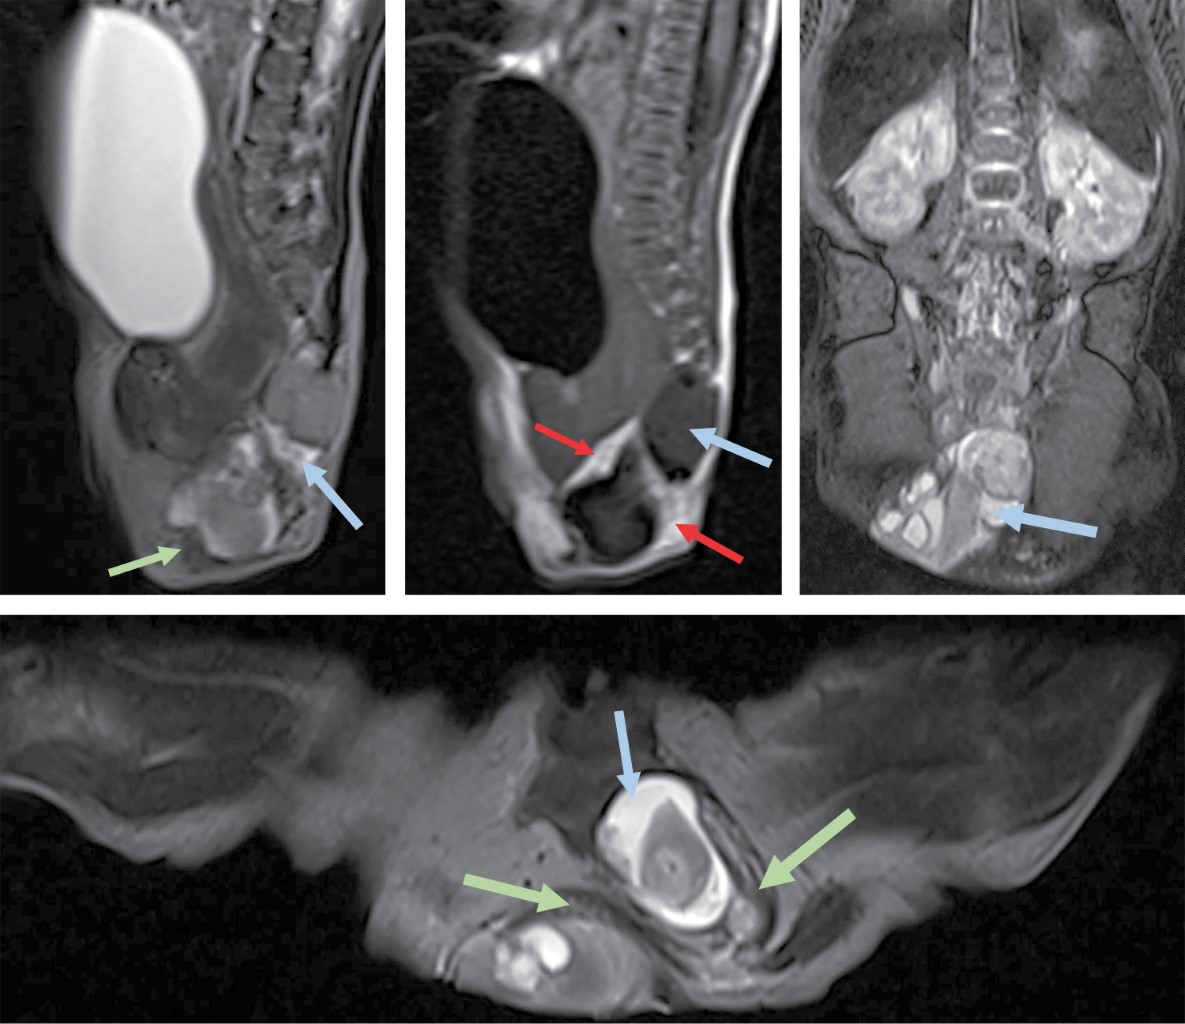

El abordaje diagnóstico imagenológico es esencial para demostrar la extensión intraabdominal y los efectos en las estructuras adyacentes. Los hallazgos por imagen del teratoma van acordes a sus componentes. Por radiografía se observará una masa de dimensiones variables que puede estar asociada a calcificaciones.10 El ultrasonido mostrará una masa de ecotextura heterogénea con presencia de focos ecogénicos de calcificaciones y grasa así como áreas quísticas anecoicas. El modo Doppler color demuestra que los componentes sólidos presentan vascularidad de moderada a alta.10,11 La tomografía computarizada muestra una masa con densidad heterogénea por sus componentes de grasa, calcio, tejidos blandos y niveles de líquido. El medio de contraste muestra un patrón de reforzamiento variable en los componentes sólidos. La resonancia magnética presenta hallazgos con intensidad de señal heterogénea. En T1 la grasa se aprecia hiperintensa, los tejidos blandos isointensos, el componente quístico hipointenso y el calcio marcadamente hiperintenso. En T2 se observa el componente quístico hiperintenso y el calcio marcadamente hipointenso. El T1 con contraste presenta un reforzamiento heterogéneo del componente sólido.3,10 Los hallazgos por imagen no pueden predecir subtipos histológicos de tumores, pero existen características de benignidad y malignidad. El componente quístico, las calcificaciones y el contenido graso prominente corresponden a hallazgos más comúnmente observados en lesiones benignas. La hemorragia y/o necrosis dentro de la masa, mayor componente sólido y realce heterogéneo con contraste son más sugestivos de malignidad.3,6 El diagnóstico prenatal se realiza con ultrasonido obstétrico y/o con resonancia magnética fetal, identificando una masa sacra heterogénea con componentes quísticos y sólidos.2,3 Postnatalmente la resonancia magnética permite la diferenciación de tejidos, extensión intramedular y pélvica, siendo superior a la tomografía computarizada al no exponer a una dosis de radiación ionizante.12 Se debe realizar diagnóstico diferencial principalmente con mielomeningocele, lipomas, hemangiomas, quiste pilonidal y epidermoide.2,7 El neonato puede presentar complicaciones cardiacas, anemia e hidrops fetal. Durante el parto puede ocurrir ruptura del teratoma y hemorragia al ser altamente vascular. Si es suficientemente grande puede ocasionar efecto de masa en estructuras adyacentes.2,3,13 El tratamiento es principalmente quirúrgico, ya sea prenatal o postnatal. La cirugía fetal intrauterina es una opción en fetos de alto riesgo como los productos con hidrops fetal. Postnatalmente la resección quirúrgica temprana se realiza para evitar progresión a malignidad y recurrencias. Los pacientes con teratoma maligno requieren manejo combinado de cirugía, quimioterapia y radiación.3,14

Paciente femenino de 32 años de edad sin antecedentes de importancia. Tomó ácido fólico previo al embarazo. Gesta dos, cesárea uno. Su primera consulta del embarazo actual fue a las 7.2 semanas de gestación (SDG) con longitud cráneo caudal acorde a la edad gestacional estimada por fecha de última menstruación. En la semana 12 se realizó ultrasonido estructural donde se observó aparente defecto a nivel sacro que parecía tener continuidad con médula espinal. En el ultrasonido a la semana 16 se apreció una imagen de contenido anecoico en la región sacra y con aparente continuidad al canal medular, en probable relación con mielomeningocele (Figura 1). En la semana 20 se realizó amniocentesis y posteriormente microarreglos encontrando complemento cromosómico 46 XX, sin alteraciones en las regiones analizadas. Se realizó tamiz de glucosa y curva de tolerancia a la glucosa en la semana 27 diagnosticando diabetes gestacional, sólo requirió manejo dietético. En la semana 26 se realizó ultrasonido identificando en región glútea una imagen con ecotextura heterogénea de predominio anecoico, con medidas aproximadas de 3.3 × 3.2 cm, que no comprometía genitales y parecía corresponder a un teratoma sacro. Se realizan seguimientos ultrasonográficos con Doppler fetal y pruebas de bienestar fetal hasta el término. A las 38.2 SDG nace por cesárea producto femenino con peso de 2,669 g y talla de 48 cm. Llora y respira al nacer, se dan maniobras básicas de reanimación. Se califica con APGAR 9/9 y Silverman Anderson de 0. Ingresa a terapia intermedia. En la exploración física neurológicamente no mostró alteraciones, la fuerza y sensibilidad de las extremidades estaba conservada, sin movimientos anormales. En la región sacra se identificó una masa con tamaño aproximado de 2 × 2.5 cm que presentó sangrado en capa, la cual de forma atípica no tenía una cobertura de piel (Figura 2). Se realizó radiografía de pelvis, ultrasonido abdominal, transfontanelar y de región sacra. Se tomó radiografía anteroposterior y lateral de pelvis que reveló integridad de los cuerpos sacros y los elementos del arco posterior sin alteraciones aparentes así como una masa con densidad de tejidos blandos inferior a la región del sacro (Figura 3). En el ultrasonido abdominal no se reportaron alteraciones, se valoró la vejiga y riñones, mismos que mostraron situación, morfología y ecogenicidad normales. El ultrasonido transfontanelar no mostró anomalías. Se realizó rastreo con transductor lineal multifrecuencia en escala de grises y con modo Doppler color de la columna lumbosacra (Figura 4). Se decidió realizar resonancia magnética para mejor caracterización de la extensión de la masa descrita. Se efectuaron secuencias multiplanares de la columna lumbosacra y panorámica sagital de la columna completa (Figura 5). Se realiza la resección completa de la tumoración, respetando estructuras pélvicas y lográndose una cobertura completa sin tensión de la herida. Adecuada recuperación postoperatoria, por dehiscencia parcial de herida se maneja sistema VAC ambulatorio, el cual es una terapia no invasiva que utiliza presión negativa sobre la herida para ayudar a la cicatrización en un medio húmedo y cerrado, lo que favorece la angiogénesis, el tejido de granulación y disminuye la colonización bacteriana (Figura 6). Niveles séricos de alfa fetoproteína y fracción beta de gonadotropina coriónica preoperatorios normales. El reporte de patología reveló teratoma inmaduro (elementos inmaduros menores de 1%), superficie externa con piel ulcerada. Después de un año de vigilancia, no hay datos de recidiva clínica o por laboratorio.

La caracterización por imagen clásica del teratoma consiste en una masa heterogénea, que por su origen embriológico (tres capas germinales), presenta componentes sólidos y quísticos, con áreas de tejido graso y áreas de calcificación,1-3 los cuales se demostraron en nuestro caso mediante el ultrasonido y la resonancia magnética.

La evaluación de la extensión de la tumoración es muy importante para planear el tratamiento quirúrgico, idealmente se debe realizar con estudios de imagen seccionales como la resonancia magnética o la tomografía computarizada, se prefiere la resonancia para evitar la exposición a radiación ionizante y por su excelente diferenciación entre tejidos.3,12 De acuerdo a la clasificación de Altman, nuestro caso correspondió a un teratoma sacrococcígeo de tipo III,9 por lo que el componente presacro era de pequeñas dimensiones y no ocasionó efecto de masa significativo en las estructuras adyacentes. El ultrasonido abdominal no mostró datos de hidronefrosis obstructiva. Asimismo, durante la exploración física las extremidades inferiores no mostraron alteraciones en su fuerza ni presencia de movimientos anormales en el contexto de la hipoplasia de músculos pélvicos y luxación de cadera asociada con el teratoma sacrococcígeo.13